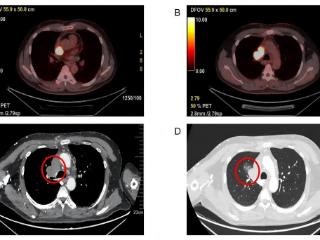

罕见!巨大肿瘤如藤蔓般长进心脏 苏大附二院完成超高难度心-肺部联合手术为患者架起新生之桥